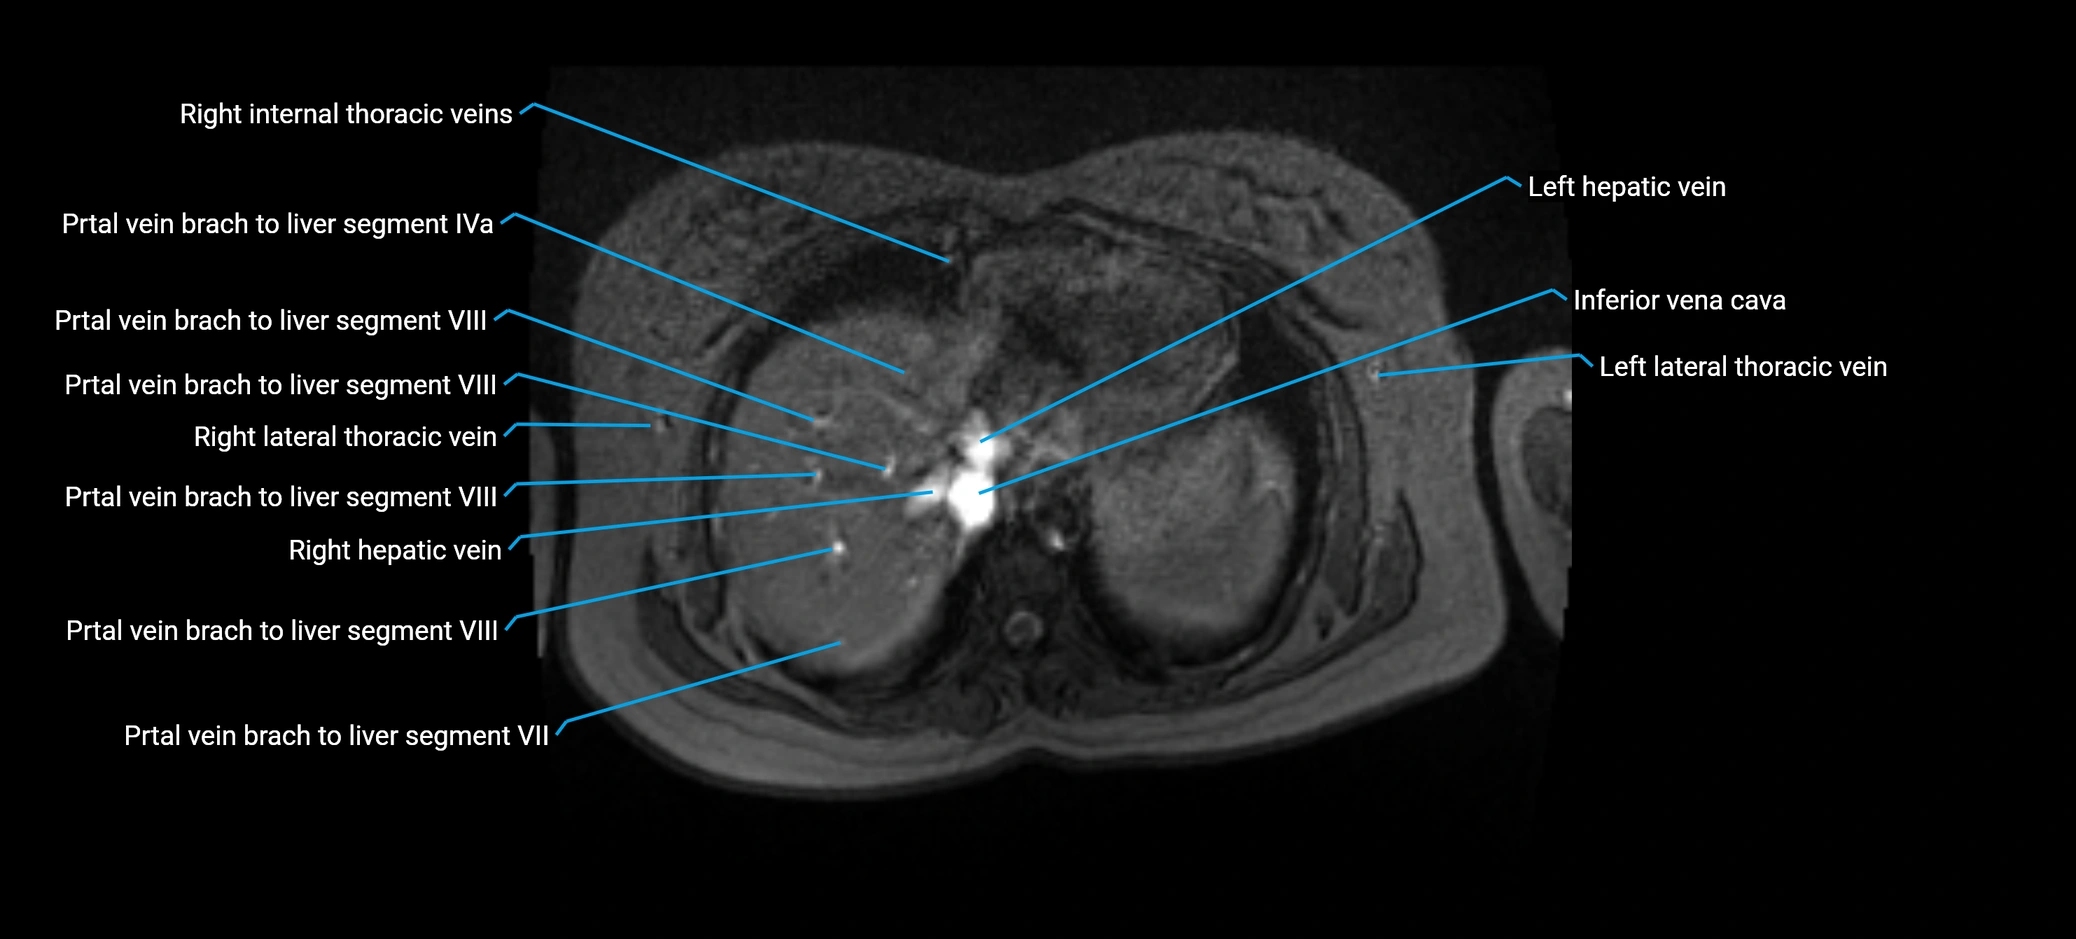

MRV TOF (Time-of-Flight MR Venography):

• Appears as a bright, high-signal vascular channel representing flowing blood

• Clearly shows branching pattern of right portal vein into anterior and posterior branches

• Best in coronal or axial reconstructions for segmental mapping

• No need for contrast, relies on flow-related enhancement

Post-Contrast T1 Fat-Sat GRE:

• Enhances brightly and homogeneously during the portal venous phase

• Clearly delineates branching into segments V and VIII

• Best sequence for evaluating patency, caliber, and anatomic variants

• Early arterial phase: minimal enhancement

• Delayed phase: gradual washout but still brighter than hepatic parenchyma